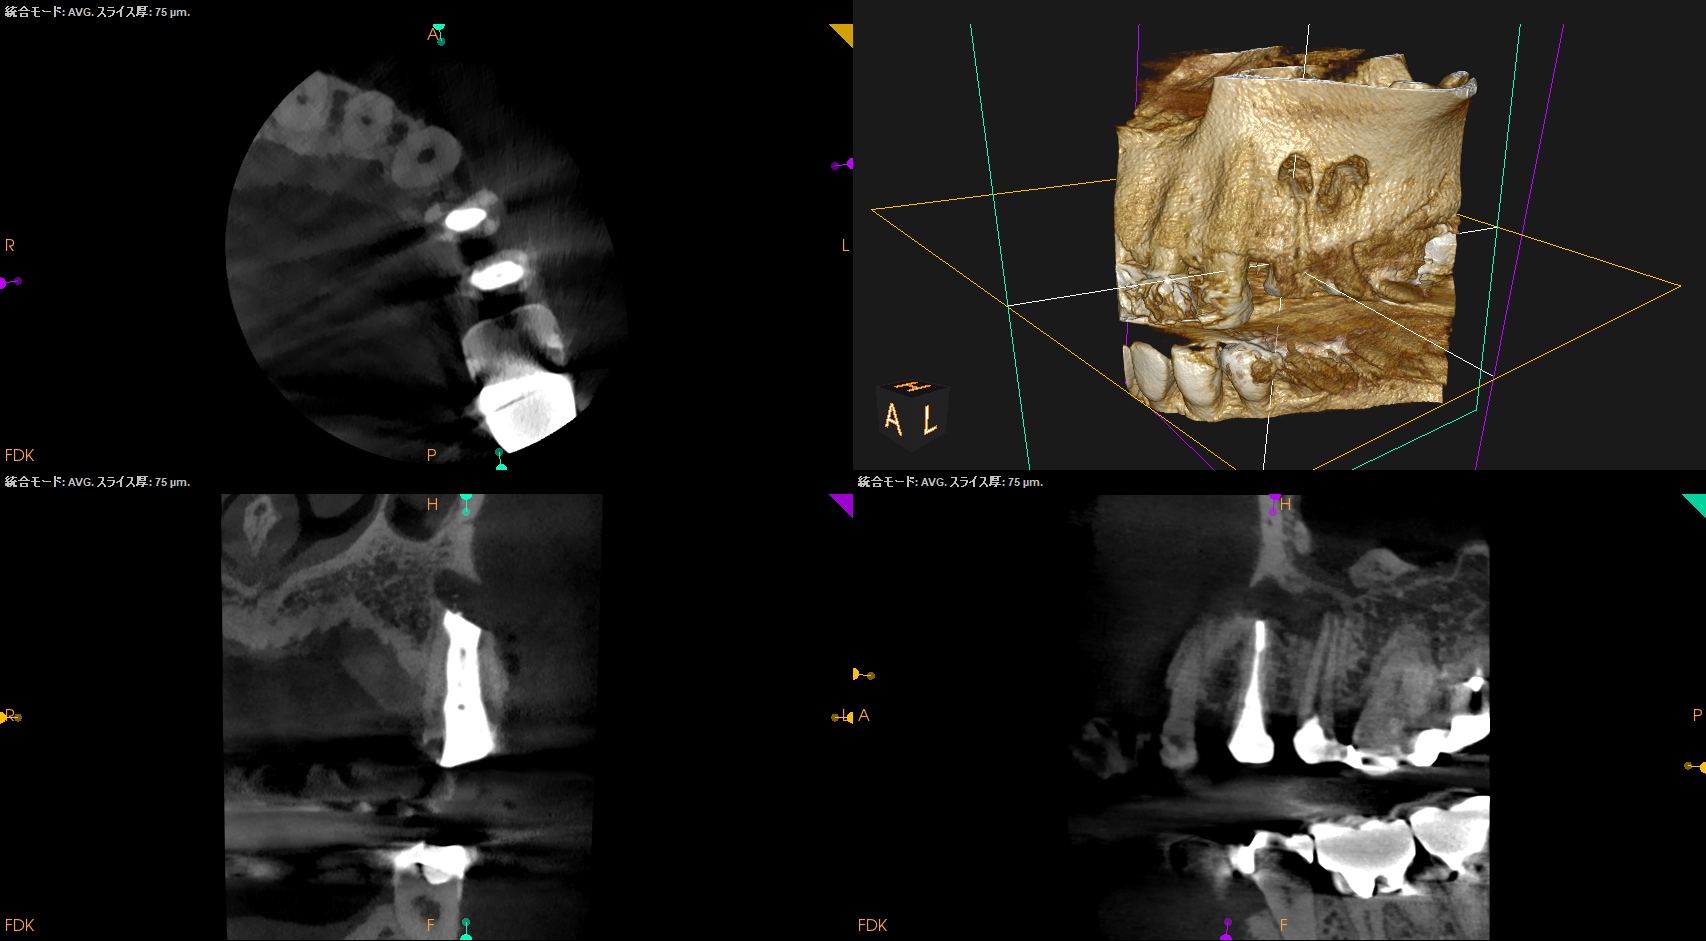

術後にPA, CBCTを撮影した。

#12

#13